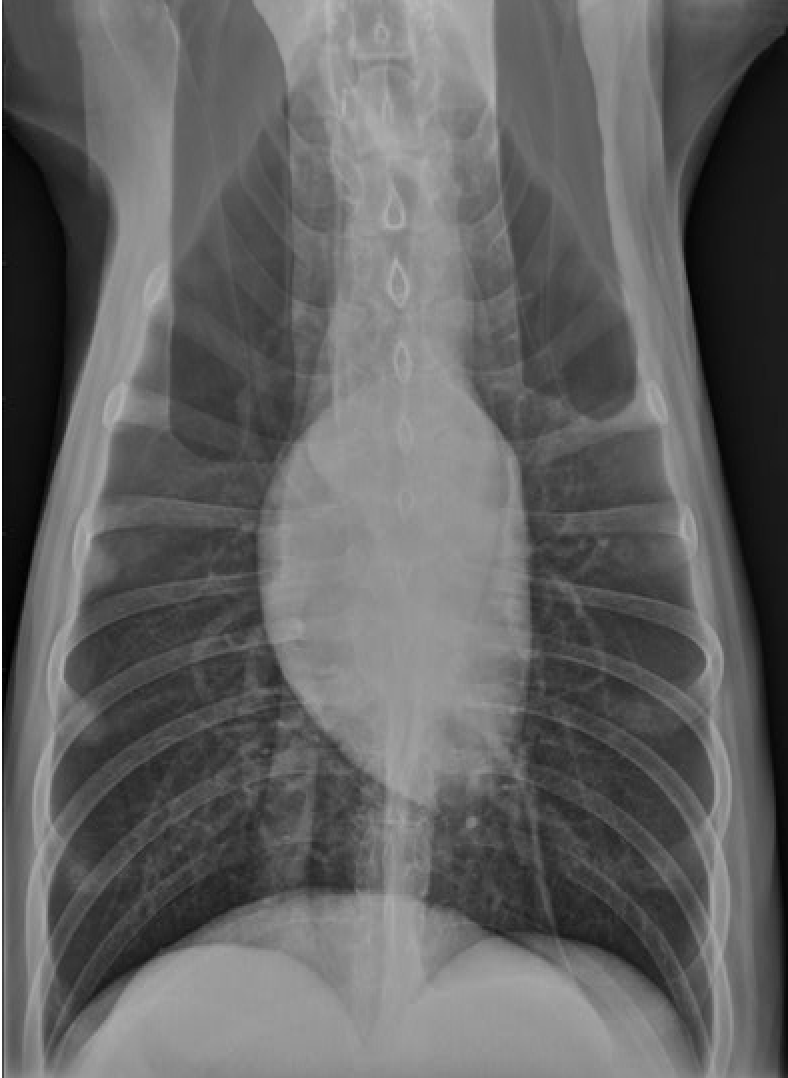

identify A, B and C

A= left atrium

B= right ventricle

C= trachea

identify the structures

RA: right auricle (atrium)

RV: right ventricle

LV: left ventricle

LA: left atrium

A: aorta

C: caudal vena cava

T: trachea